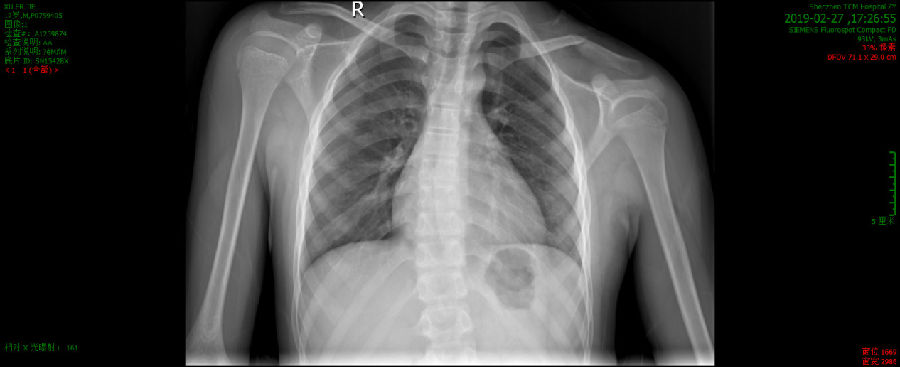

查胸部正侧位示:

1、左锁骨中段骨折。

2、所示左肩关节对合欠佳。

多考虑体位所致,关节脱位待排,请结合临床。

术前左锁骨X线